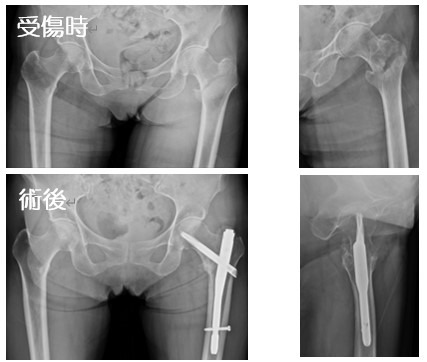

2020-07-21 手外科・外傷 ページ内リンク 髄内釘(short femoral nail) Sliding hip screw 大腿骨頚部骨折(骨接合術) 大腿骨頚部骨折(人工骨頭挿入術) 腿骨転子部骨折(髄内釘) 髄内釘(short femoral nail) Sliding hip screw 大腿骨頚部骨折(骨接合術) 大腿骨頚部骨折(人工骨頭挿入術) 腿骨転子部骨折(髄内釘) 露口 和陽 外傷・手外科部長 整形外科手外科・外傷 詳しく見る 関 謙太朗 整形外科肩関節外科手外科・外傷 詳しく見る 関連ページ 手外科・外傷 一覧へ戻る